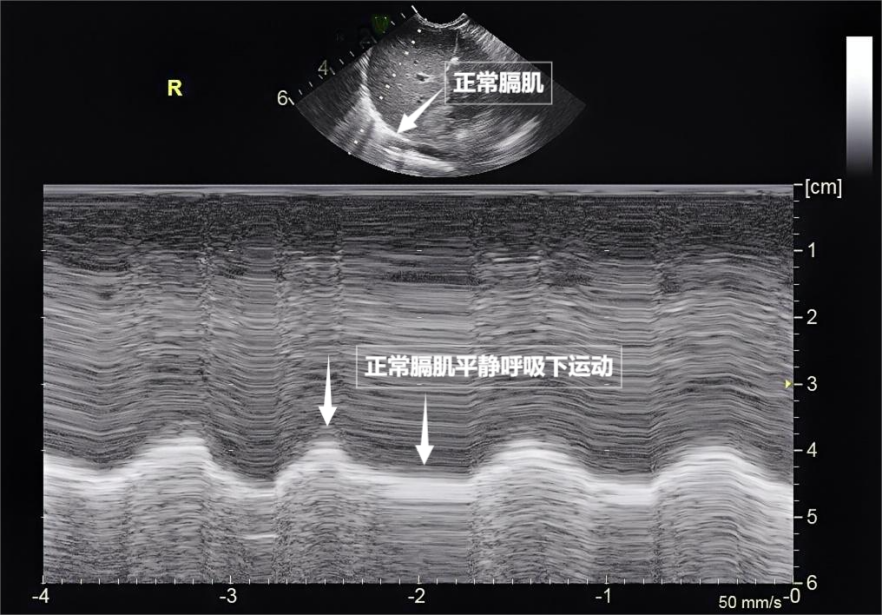

呼吸看似简单,实则是多组肌肉精密配合的"团体操"。肺部超声不仅能观察肺的形态,更能通过实时动态影像,"捕捉"这些呼吸肌的活动状态,为评估呼吸功能提供独特视角。膈肌是呼吸肌的"总指挥",位于胸腔与腹腔之间。平静呼吸时,膈肌收缩下沉,胸腔容积扩大,空气自然吸入;舒张时,膈肌回升,肺部弹性回缩完成呼气。超声下可见膈肌呈光滑弧形,随呼吸规律上下移动( 见下图 )。肋间外肌则是"肋间隙的升降机",收缩时上提肋骨,扩大胸腔前后径,辅助吸气。这对"黄金搭档"承担了日常呼吸70%以上的工作量,是维持呼吸的"主力军"。

图为正常膈肌超声表现